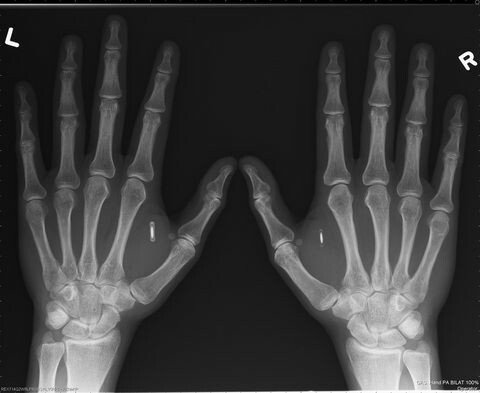

자신의 신체에 임플란트칩이 느껴지는

마인드컨트롤전파무기피해자는

TI (TargetedIndividuals)로 불립니다.